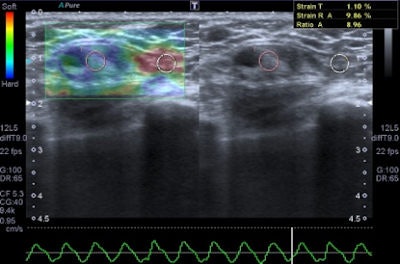

Freehand ultrasound, or compression elastography ("strain elastography"), is based on the application of a compressive force to the breast and on the measurement of the shape-deforming effect, thus providing a value of lesion stiffness compared with that of surrounding tissues, the authors wrote. A slight manual compression/decompression is applied using a conventional transducer, or the deformation may be determined by respiratory movements.

"The technique allows only for qualitative and semiquantitative assessments of a lesion because the force exerted by manual compression is unknown to the equipment, thus allowing only the calculation of the deformability ratio (strain ratio) and not the absolute elasticity," Ricci wrote and colleagues.

Benign lesions are described at elastography as lesions with a low color map score (score 1-2), while the best cut-off point for discriminating benign from malignant masses falling at the 3-4 boundary of color map classification, according to the Ueno-Itoh score system. Cysts often appear as hard and low deformable lesions, commonly represented with a blue pattern at the color map and with a high strain ratio because of their low compressibility.

Editor's note: In the image on our home page, the shape and infiltration of the breast tumor is demonstrated in 4D Hitachi real-time tissue elastography (HI-RTE). Image courtesy of Hitachi Aloka, previously published in the ECR Today newspaper.